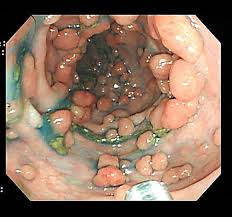

スレ画は壷井くんですw

さっき大腸カメラ予約したわ。